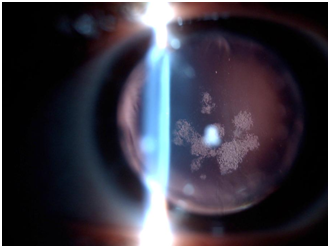

In the following months, the extraction of points in several sessions was carried out, producing a remarkable variation in the morphology of the corneal button, as can be seen in the following axial maps (Figure 3).2 Finally, four months later, the extraction of points is finished, leaving two intrastromal points. At this point, the VA of the patient is 0.4 dif, with a refraction in glasses of 180º -5.00 +2.00. The difficulty in the adaptation of contact lens that will be sought, lies in the morphological change of the cornea, since it is observed an encurvamiento of the same. Initially, the adaptation of corneal semi rigid lens (KA4 Reverse BTC) is attempted, but the lens is so raised in the lower area (it practically rests on the eyelid margin itself), which falls too easily. The power of the lens is +2.00/-1.25 reaching the patient an AV of 0.3. The lens is rectified looking for a closing of it. This improves the adaptation in the lower area and improves stability, but upper quadrant bubbles are formed between 2h and 3h (Figure 4), (Table 1A) (Table 1B). During subsequent visits, the formation of a posterior subcapsular cataract is observed, probably as a consequence of the surgery itself and the catatogenic effect of the medications prescribed as treatment (Figure 5). This adds one more difficulty to the prognosis of an acceptable VA2, which up to now was 0.3 with an unstable corneal lens. At this point, the corneal lens adaptation is abandoned and the semi-scleral lens is adjusted to 7.30, power -6.50 and diameter 16.50. Initially the patient shows greater comfort than with corneal lens and better vision, being the AV of 0.4, which with overrefraction of +1.00 D improves to 0.5+.

Figure 5 Posterior subcapsular cataract.